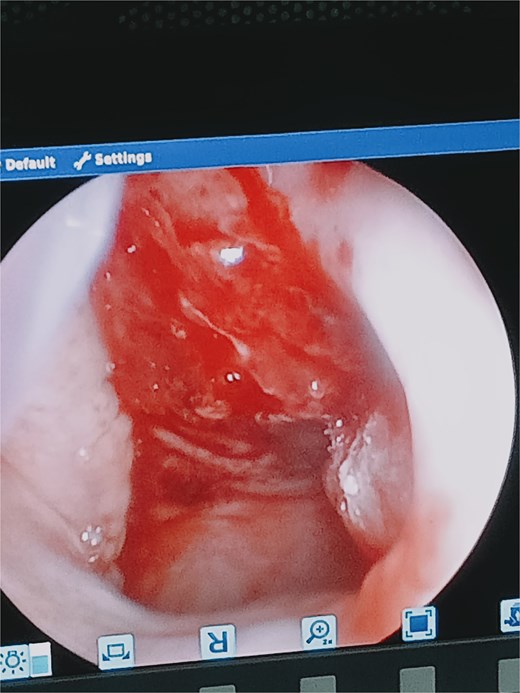

She was taken for examination under anesthesia where nasopharyngoscopy demonstrated extensive mucosal lacerations involving the inferior turbinate, nasal floor, nasopharyngeal roof and posterior wall, with active bleeding (Fig. 3). Additional traumatic injuries were observed on the soft palate and the left posterior tonsillar pillar (Fig. 4). Blood clots were evacuated, through irrigation, and hemostasis was achieved through gauze compression, suturing, and electrocautery, followed by anterior and posterior nasal packing. She received two units of blood and was stabilized before transfer to the pediatric oncology ward.

Nasoendoscopy through the left nostril showing mucosal injury on the roof and posterior wall of the nasopharynx, with active bleeding.